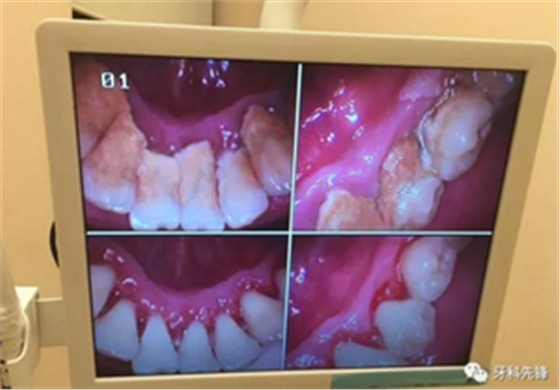

臨床上確實存在這樣的情況,但是作口腔醫(yī)生,我為一名可以負(fù)責(zé)任的告訴大家,如果不清除掉牙結(jié)石后果會更加嚴(yán)重,甚至有脫落的風(fēng)險。原理是什么呢?因為牙結(jié)石、牙菌斑的破壞能力是極其強(qiáng)大的,只要它存在就會一直不斷的刺激壓迫牙齦,時間久了則會導(dǎo)致牙齦紅腫出血、牙槽骨吸收、牙齦萎縮、牙齒松動甚至脫落等情況,這是一個緩慢發(fā)展的病變過程,單純的靠牙結(jié)石撐住牙齒不讓其出現(xiàn)病理性移動從根本上講是極其不現(xiàn)實的,有點(diǎn)兒“掩耳盜鈴”的意味,不僅撐不住反而會加快牙齒松動、脫落。很可怕吧,尤其是對于我們成年人來說,現(xiàn)有且僅有的一副恒牙竟然還被牙結(jié)石牙菌斑禍害成這個樣子,應(yīng)該算是一種不幸吧!